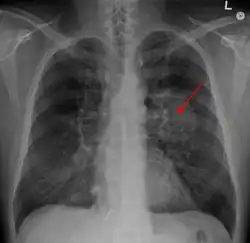

Tumeur du poumon

Les tumeurs du poumon sont les tumeurs (néoplasies, néoplasmes) se développant à partir du poumon.